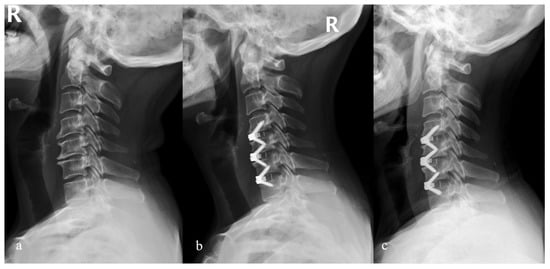

2. Materials and Methods

3. Results